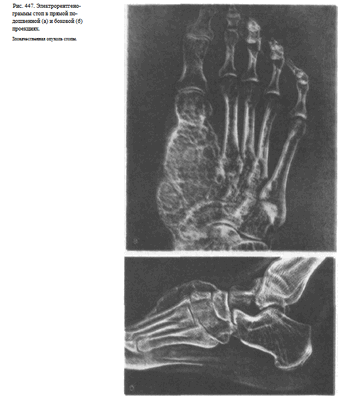

Изменения мягких тканей особенно наглядно видны на электро-рентгенограммах (рис. 447, а, б).